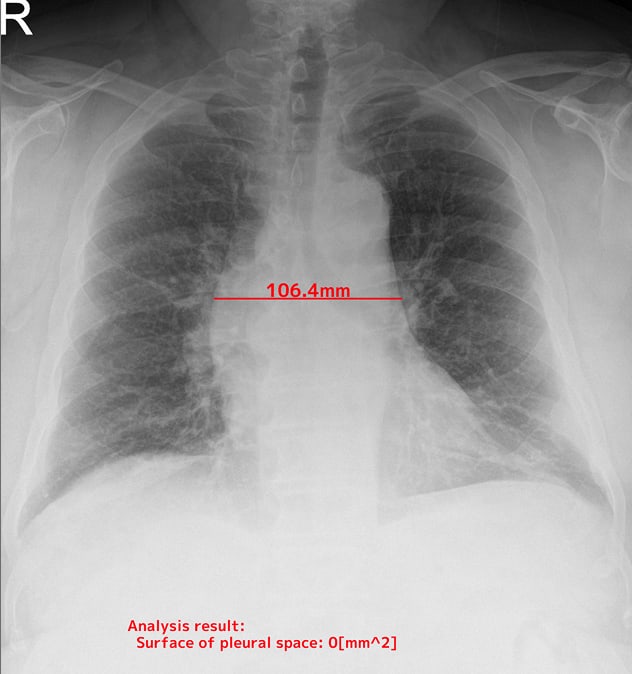

- 胸腔内の空気含有面積

自動計測機能